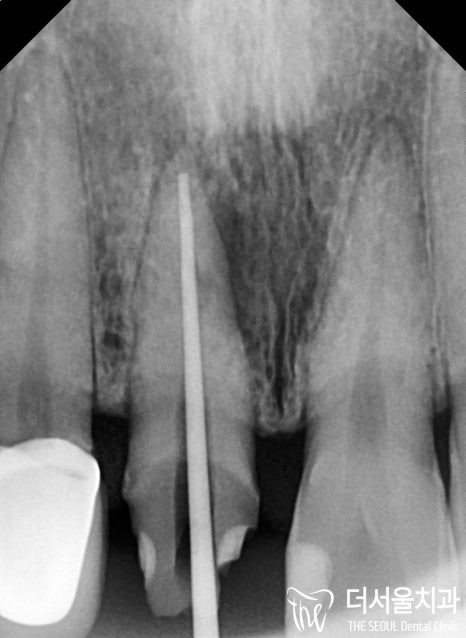

그래서 결과 부터 보여드린거고

저런 부근관을 채우기 전에는,

메인 신경관 부터 먼저 꼼꼼히

소독을 하면서 뿌리로 부터 치관까지

꼼꼼히 충전을 해나가게 됩니다.